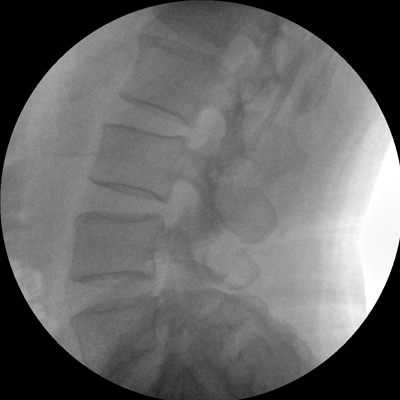

專(zhuān)業(yè)的圖像處理系統(tǒng),為您提供高分辨率、高灰階圖像。